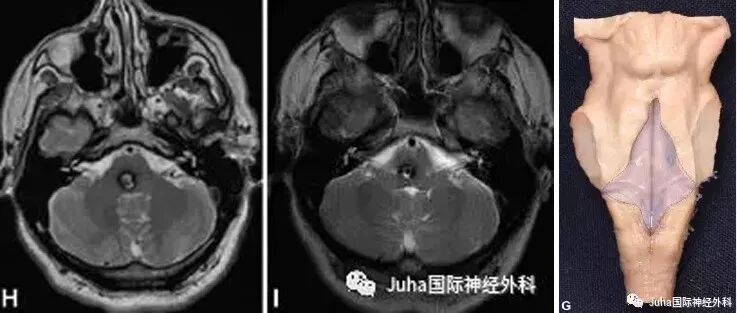

MRI显示:脑干海绵状血管瘤主要位于桥脑右侧后方

病灶位于右侧后方,不考虑眶颧入路。

若要经第四脑室底且不损伤任何神经组织而干净利落地到达病灶,就该病例来说,枕下膜帆入路是一个合适的选择。

1、病灶最接近四脑室底部;

2、病灶位于桥脑上部,接近中脑导水管,高于面丘平面,既桥脑手术安全区域的SCZ区。

因此,术者采用枕下膜帆入路。术中证实病灶位于面丘平面上方,在SCZ区域内,术后患者恢复情况也进一步证实该入路的合理性。